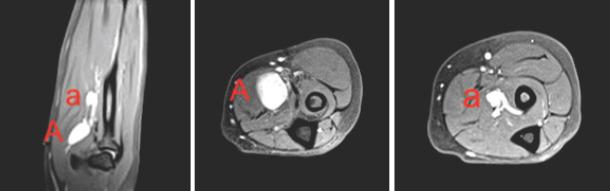

这是一名36岁右利手女性的病例,她因前臂有多年疼痛性肿块病史前来我们诊所就诊。体格检查时,她有一个可触及的疼痛性肿块,Tinel征阳性,疼痛和感觉异常沿正中神经分布向远端放射。随后的MRI扫描显示,在主要病变远端与正中神经相邻处有第二个较小的肿块,两者似乎均为正中神经的施万细胞瘤。在本病例报告中,除了回顾关于影响上肢的多个施万细胞瘤的文献外,我们还讨论了患者的表现、诊断检查和影像学发现、手术技术及病理结果。